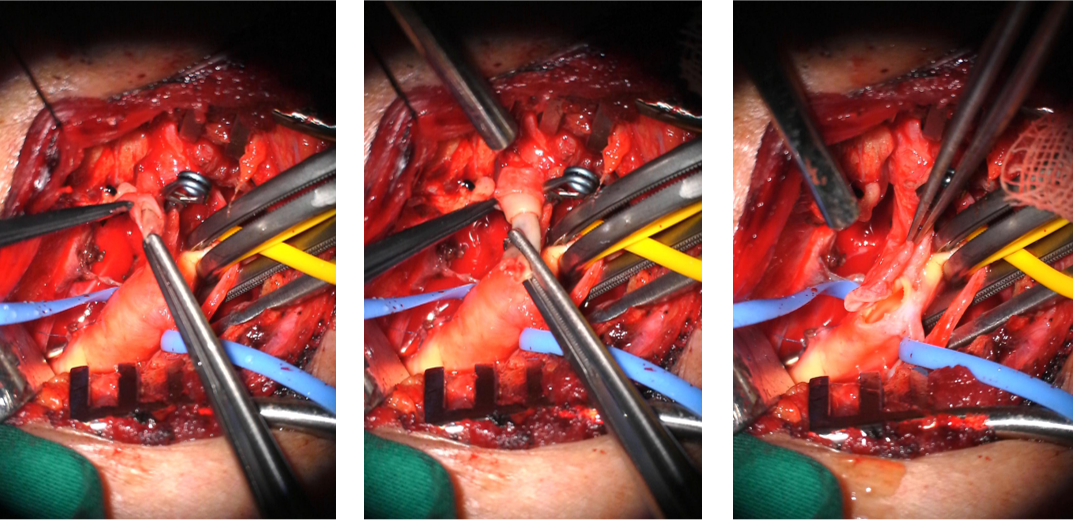

M,60,左侧小脑梗死,左椎动脉V1-V2段长段闭塞

椎动脉外翻剥脱、椎动脉-锁骨下动脉端侧吻合

椎动脉-锁骨下动脉端侧吻合

介入开通